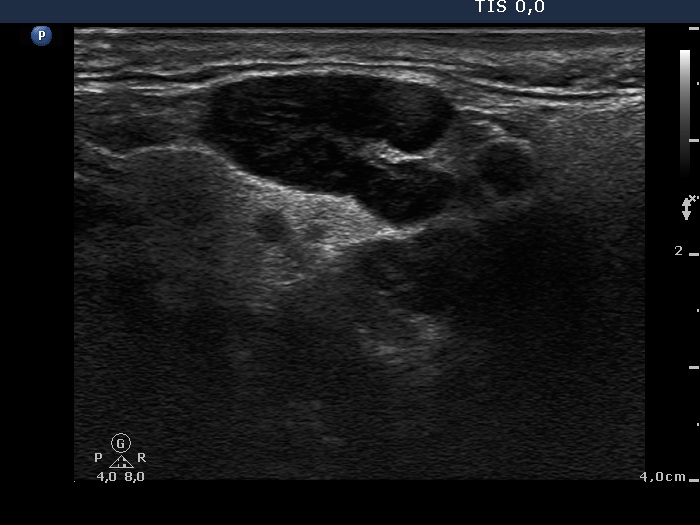

Thyroid cancers - case 1574 (ultrasonographic picture 8)

Left submandibular area, longitudinal scan. It is doubtful whether this is a cystic or a deeply hypoechoic lesion.